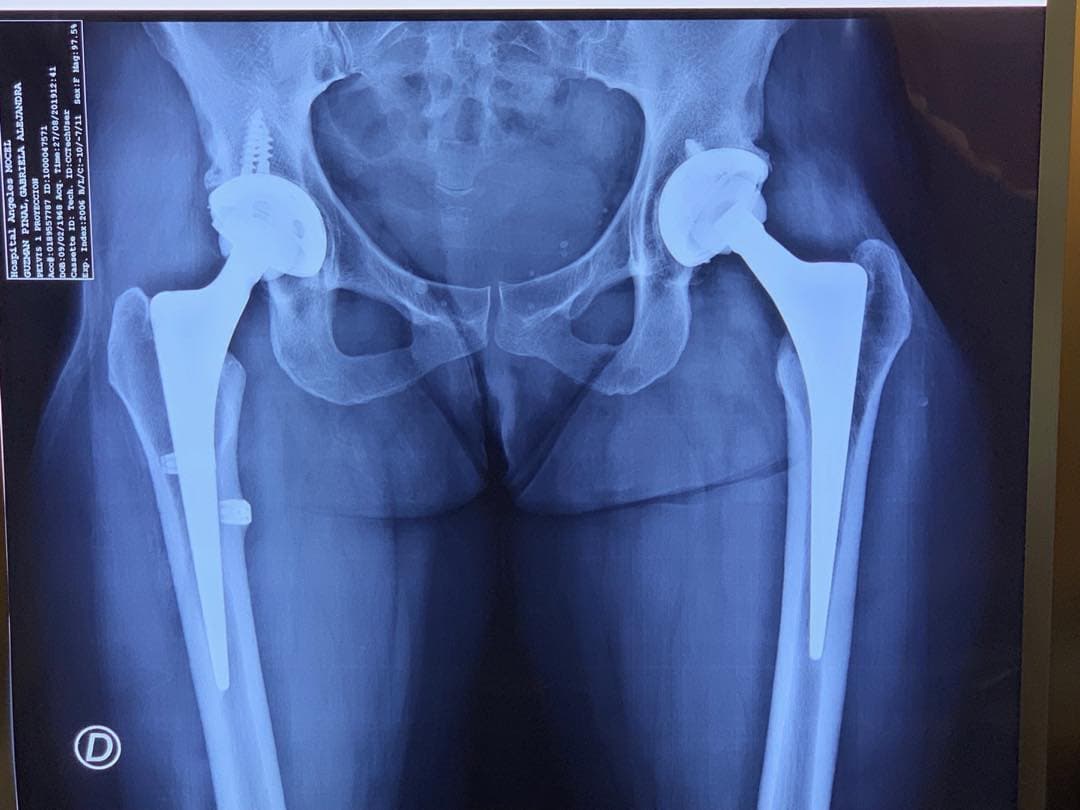

Alejandra Guzmán muestra su prótesis en la cadera

En agosto, de 2019, Alejandra Guzmán tomó sus redes sociales para mostrar la prótesis de titanio que le fue colocada en su cadera a consecuencia de las más de 20 cirugías a las que se sometió tras un mal procedimiento estético para aumentar el tamaño de sus glúteos. “Soy de titanio”, expresó en Instagram.